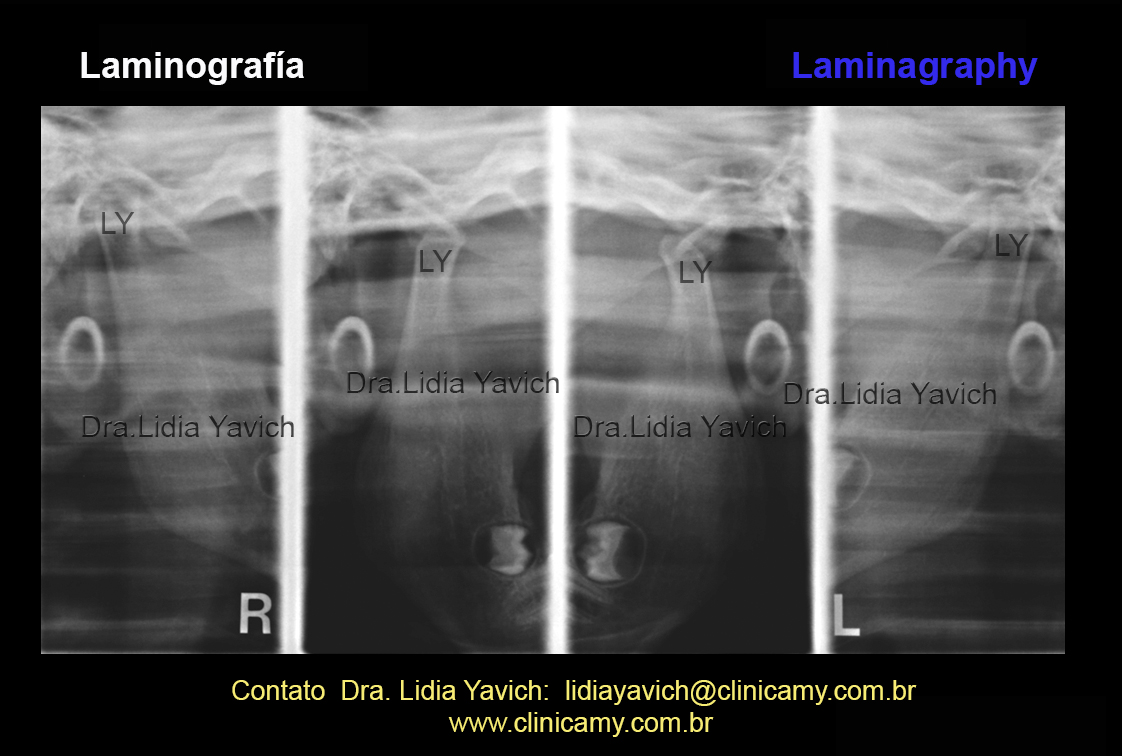

8 laminografia

A laminografia das articulações temporomandibulares em boca fechada e aberta é considerada como uma radiografia panorâmica das articulações temporomandibulares.

A laminografia das articulações temporomandibulares não pode ser comparada com uma tomografia computadorizada das articulações temporomandibulares, mas é um exame básico para uma primeira informação das articulações temporomandibulares.

8 laminografia corNesta mesma imagem com destaque de cor podemos apreciar a retroposição da ATM do lado esquerdo, a mudança do eixo de crescimento deste mesmo lado e a perda de espaço articular em ambos os lados.

9 ampliação laminografia Ampliação da imagem da laminografia com realce de cor.Boca fechada, lado direito e esquerdo.

Esta imagem ampliada das articulações temporomandibulares em boca fechada, direita e esquerda NÃO  MOSTRA O ESTADO DO DISCO ARTICULAR NEM DOS LIGAMENTOS.  11 ressonancia Resonancia Nuclear Magnética